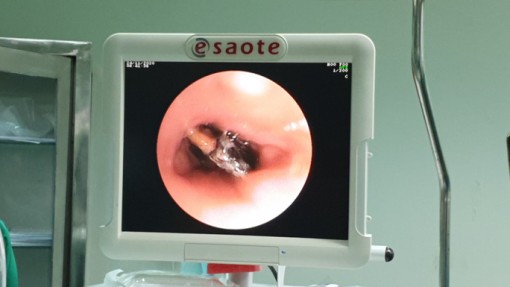

• Căng thẳng lấy hạt hồng xiêm nằm 27 năm trong phế quản của người phụ nữ

Căng thẳng lấy hạt hồng xiêm nằm 27 năm trong phế quản của người phụ nữ

25-11-2020 15:53

Các bác sĩ của Bệnh viện Đa khoa trung ương Cần Thơ vừa thực hiện thành công nội soi phế quản lấy hạt hồng xiêm nằm trong phế quản suốt 27 năm của nữ bệnh nhân.